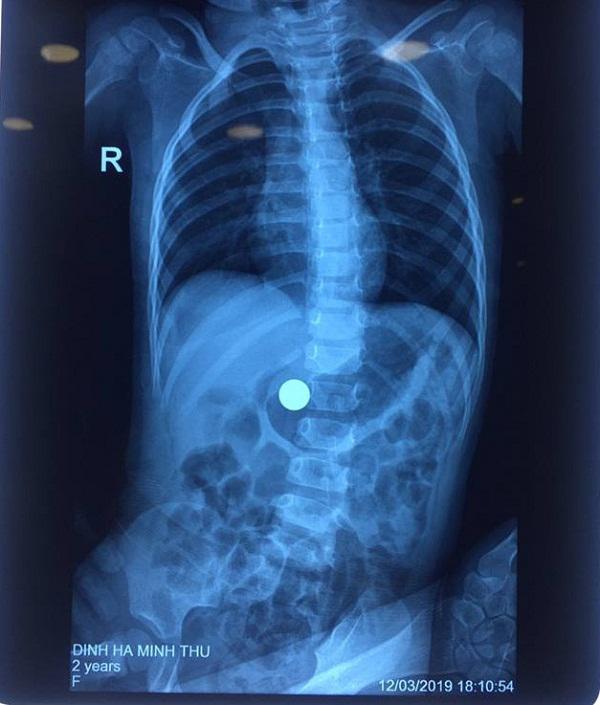

Qua siêu âm các bác sĩ phát hiện bé bị hóc dị vật do nuốt phải viên bi sắt mắc tại cổ họng, gây khó thở, đầy bụng. Mặc dù quãng đường từ nhà đến bệnh viện không xa nhưng do gia đình sơ cứu không đúng cách nên khi đến bệnh viện thì viên bi đã vào hẳn bên trong ổ bụng.

Tại bệnh viện, sau khi siêu âm và chụp X-quang các bác sĩ phát hiện vùng bụng của bệnh nhi có dị vật là viên bi sắt có kích thước lớn, nếu để lâu trong bụng bị thức ăn quấn quanh sẽ trở thành lõi, khối bã thức ăn lớn dần gây hẹp môn vị, có thể gây tắc ruột. Nguy hiểm hơn, viên bi sắt có thể có rỉ sét dễ gây viêm nhiễm hoặc áp xe, tổn thương đường ruột, thậm chí gây thủng ruột, hoại tử ruột nguy hiểm đến tính mạng…

Xác định mức độ nguy hiểm của tình trạng hóc dị vật ở bệnh nhi, các bác sĩ đa chỉ định nội soi qua đường thực quản để gắp dị vật cho bé. Chị My cho biết, chỉ một ngày sau nội soi gắp dị vật bi sắt, bé T. “thoát nạn”, cháu ăn uống tốt, đi vệ sinh bình thường và đã được xuất viện về nhà.